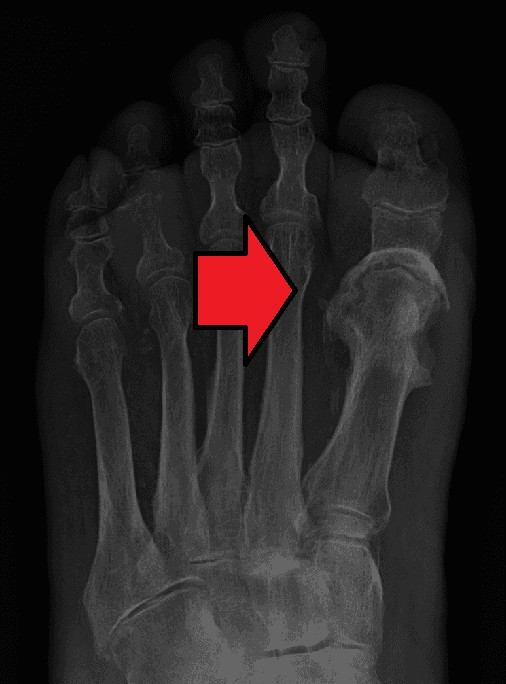

Osteomyelitis (OM) is an infection of bone. Symptoms may include pain in a specific bone with overlying redness, fever, and weakness. The long bones of the arms and legs are most commonly involved in children e.g. the femur and humerus, while the feet, spine, and hips are most commonly involved in adults. The cause is usually a bacterial infection, but rarely can be a fungal infection. It may occur by spread from the blood or from surrounding tissue. Risks for developing osteomyelitis include diabetes, intravenous drug use, prior removal of the spleen, and trauma to the area. Diagnosis is typically suspected based on symptoms and basic laboratory tests as C-reactive protein (CRP) and erythrocyte sedimentation rate (ESR). This is because plain radiographs are unremarkable in the first few days following acute infection. Diagnosis is further confirmed by blood tests, medical imaging, or bone biopsy. Treatment of bacterial osteomyelitis often involves both antimicrobials and surgery. In people with poor blood flow, amputation may be required. Treatment of the relatively rare fungal osteomyelitis as mycetoma infections entails the use of antifungal medications. In contrast to bacterial osteomyelitis, amputation or large bony resections is more common in neglected fungal osteomyelitis, namely mycetoma, where infections of the foot account for the majority of cases. Treatment outcomes of bacterial osteomyelitis are generally good when the condition has only been present a short time. About 2.4 per 100,000 people are affected each year. The young and old are more commonly affected. Males are more commonly affected than females. The condition was described at least as early as the 300s BC by Hippocrates. Prior to the availability of antibiotics, the risk of death was significant. Symptoms may include pain in a specific bone with overlying redness, fever, and weakness and inability to walk especially in children with acute bacterial osteomyelitis. Onset may be sudden or gradual. Enlarged lymph nodes may be present.